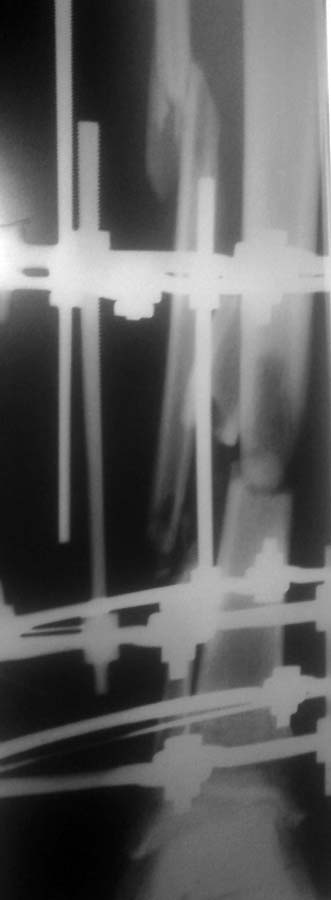

Открытый многоосколчатый перелом обеих костей голени со смещением

Попал в мотоаварию в сентябре,пролежал 10 дней на вытяжке,и 19 установили аппарат иллизарова,после чего сделали несколько корректировок

и получился вот такой результат,скажите,все ли стоит как положено?или имеет смысл обратиться в ЦИТО?С конечным результатом хожу уже с 15 октября,снимок сделали 8 ноября,и вот выкладываю

Ось (по одной проекции) выглядит приемлемо. Похоже, есть значительный дефект. Мы бы заменили аппарат на гвоздь с антибактериальным покрытием. Что предложат в ЦИТО - не знаю. И в Москве много куда еще можно обратиться, можно даже к нам приехать.